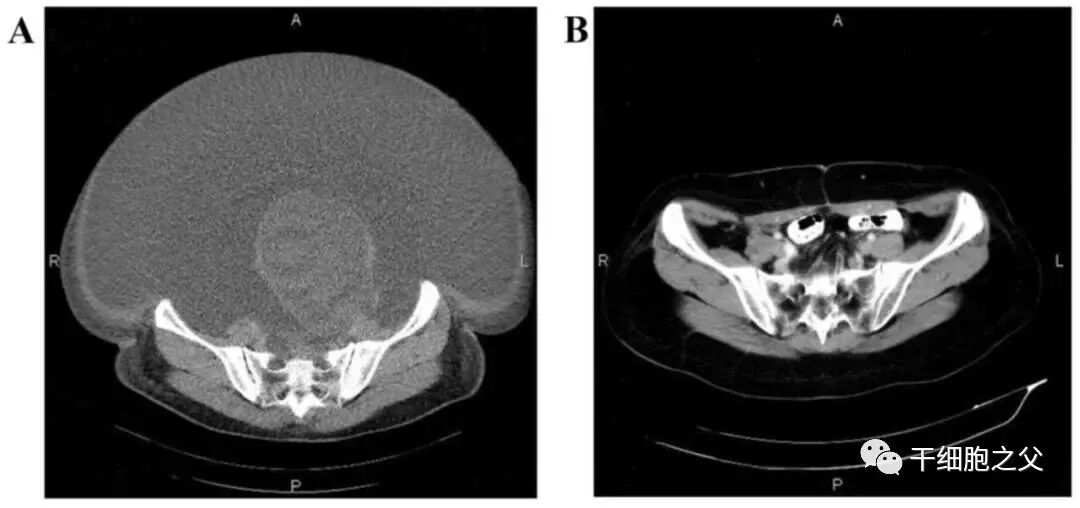

根据文献报道的案例,国内第一例接受NK细胞治疗的卵巢癌患者,是一名60岁的患者,在2015年确诊为晚期,伴有大量腹水和巨大肿瘤,在接受了体外扩增,高度活化的同种异体NK细胞的治疗后,CA125水平从11,270降至580,所有腹水都消失了。此外,CT扫描的肿块体积减小,并且没有出现副作用。

图片